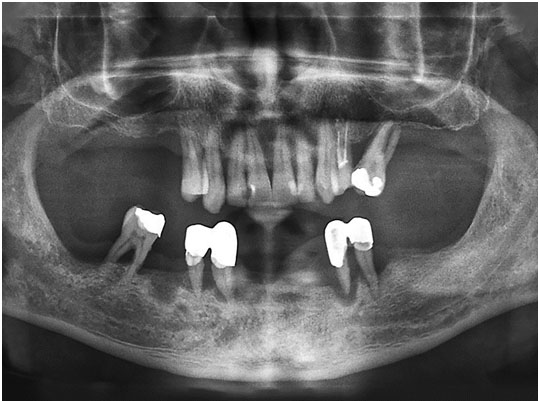

Case Report: The patient presented an increase in tissue volume in the papilla region between teeth 33 and 34, with no report of pain and with aesthetic impairment. Radiographically, no pathological changes were noted in bone and dental structures.